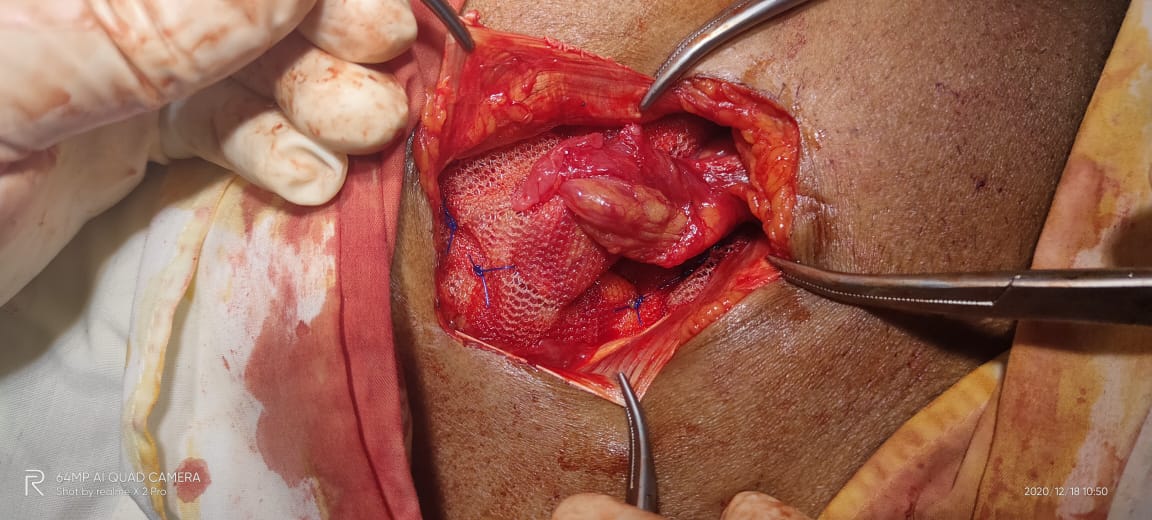

Tumors are abnormal masses of tissue that form when cells begin to reproduce at an increased rate. Both noncancerous (benign) and cancerous (malignant) tumors can develop in the liver.

The gallbladder is a small organ located just below your liver in your right upper abdomen. It stores bile, which is a liquid produced in the liver. The gallbladder releases bile into the small bowel to help break down and absorb dietary fats. Normal digestion is possible without a gallbladder.